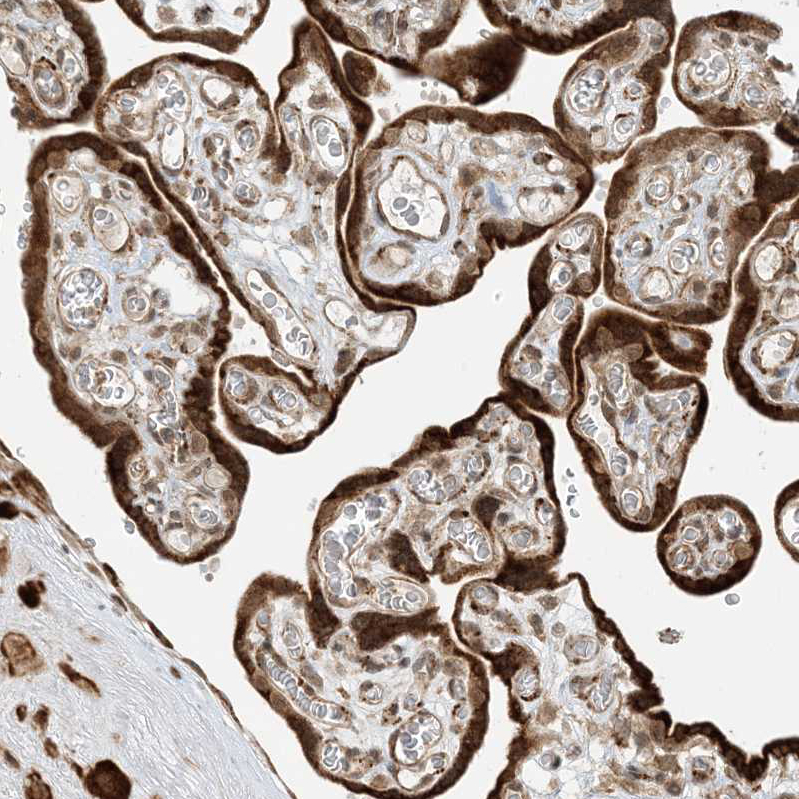

Immunohistochemical staining of human placenta shows strong cytoplasmic positivity in trophoblastic cells.